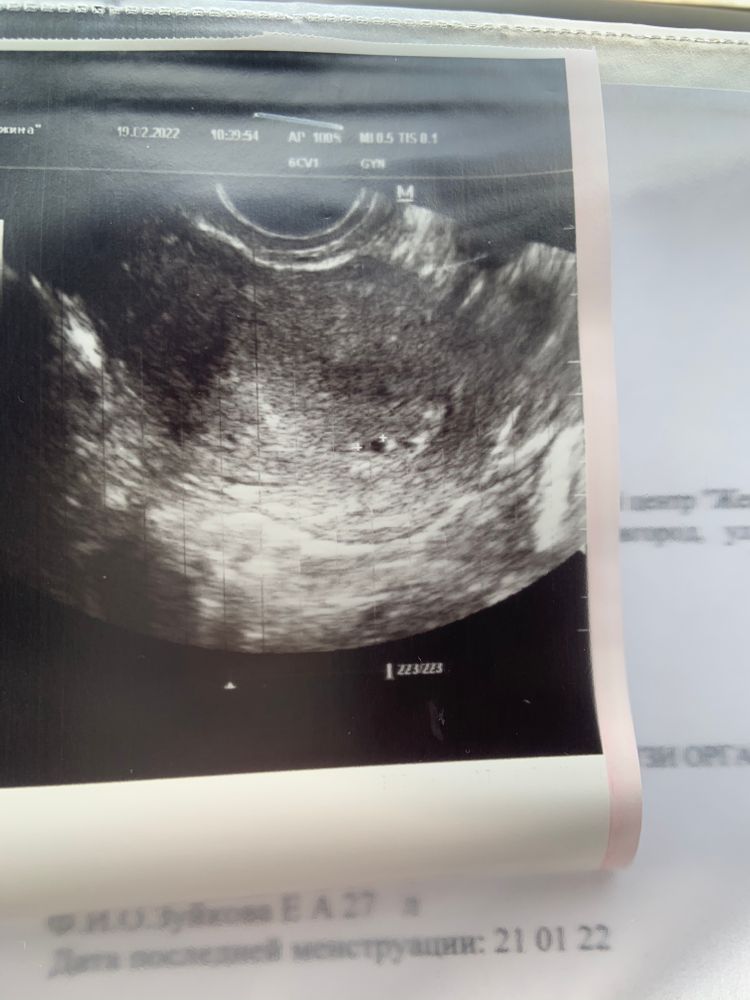

По узи плотное яицо 3,9 мм.